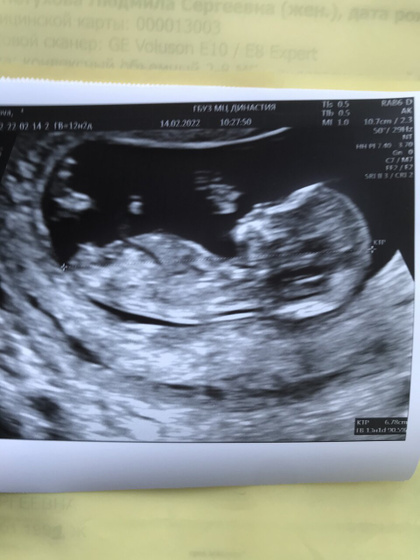

По показаниям все хорошо, беременность развивается. Спросила про пол врач сказала девочка, ничего не выросло ?с первым мне сразу сказали на этом сроке мальчик он и свои причиндалы показал, младший прятался, а тут все по другому. Дочка позировала, все показала ?

Первый скрининг я проходили в Династии врач, котороя проводила скрининг очень хорошая показывала рассказывала.

Вышла с узи села в машину показываю фото мужу он не поймёт, мое выражение лица было сдержанное он что мальчик, я молчу ? Смотрю на него он -девочка. Я говорю да, у мужа лицо в улыбке расплылось, слёзы на глазах. Мы очень хотели дочку. Наша Варечка. ❤️